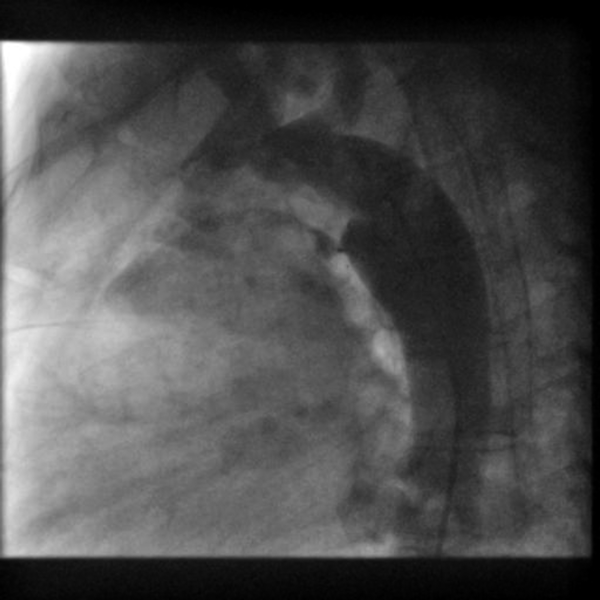

左→右短絡によるQp/Qsは1.2と推定され,心臓カテーテル検査の方針となった.身長168.6 cm,体重71.8 kg,血圧120/66 mmHg,脈拍数76回/分,経皮的酸素飽和度97%,浮腫なし,心拍整,第二肋間胸骨左縁Levine I/VI continuous murmur, bounding pulseなし,呼吸音清,腹部平坦軟,肝脾触知しない.入院時の胸部X線では心胸郭比(CTR : cardio thoracic ratio)47%と心拡大は軽度で,肺血管陰影の増強を認めなかった(Fig. 1).12誘導心電図は洞調律で心拍数60回/分,QRS軸-30°,有意な異常所見は認めなかった(Fig. 2).血液検査では,白血球9,700/µL, AST 28 U/L, ALT 36 U/L, NT-proBNP< 10 pg/mL, LDH 206 U/L, CPK 86 U/Lであった(Table 1).心エコー検査では肺動脈内連続性短絡血流があり(Fig. 3),収縮期max vel=3.7 m/sec拡張期max vel=2.9 m/secであった.また,軽度の僧帽弁逆流を認めた.左室駆出分画73%,左室流入波形(E/A=2.2 E/E′=6.9)と左室機能は保たれていた.明らかな下行大動脈の拡張期逆行性血流は認めなかった.心臓カテーテル検査では,下行大動脈からの造影でPDAはKrichenko A型(Fig. 4)に描出され,ampulla径3.5 mm, PA側2.2 mm,最狭部2.5 mm,長さ8.9 mmであった.Fick法を用いて計算したQp/Qsは1.0,肺血管抵抗値は1.08 Wood単位・m2であった.成人先天性心疾患診療ガイドライン4)に基づき,推奨クラスI,エビデンスレベルCと判断し,初回治療後34年目に再閉鎖目的で入院となった.

Fig. 4 Image of cardiac catheter

Aortography during catheterization demonstrating the patent ductus arteriosus with a residual shunt before device deployment.